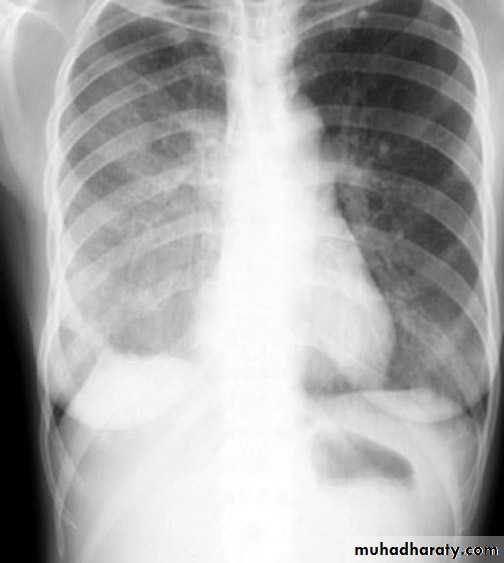

Middle lobe pneumonia

rt.upper lobe pn. Left lower lobe pn.